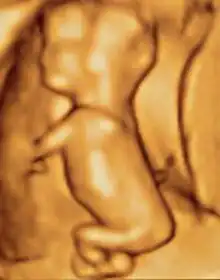

Obstetric ultrasonography is routinely used for dating the gestational age of a pregnancy from the size of the fetus, determine the number of fetuses and placentae, evaluate for an ectopic pregnancy and first trimester bleeding, the most accurate dating being in first trimester before the growth of the foetus has been significantly influenced by other factors.[22] Ultrasound is also used for detecting congenital anomalies (or other foetal anomalies) and determining the biophysical profiles (BPP), which are generally easier to detect in the second trimester when the foetal structures are larger and more developed.[23]

X-rays and computerized tomography (CT) are not used, especially in the first trimester, due to the ionizing radiation, which has teratogenic effects on the foetus.[24] No effects of magnetic resonance imaging (MRI) on the foetus have been demonstrated,[25] but this technique is too expensive for routine observation. Instead, obstetric ultrasonography is the imaging method of choice in the first trimester and throughout the pregnancy, because it emits no radiation, is portable, and allows for realtime imaging.[26]

The safety of frequent ultrasound scanning has not been confirmed. Despite this, increasing numbers of women are choosing to have additional scans for no medical purpose, such as gender scans, 3D and 4D scans.[27] A normal gestation would reveal a gestational sac, yolk sac, and fetal pole.[28]

The gestational age can be assessed by evaluating the mean gestational sac diameter (MGD) before week 6, and the crown-rump length after week 6. Multiple gestation is evaluated by the number of placentae and amniotic sacs present.[29]